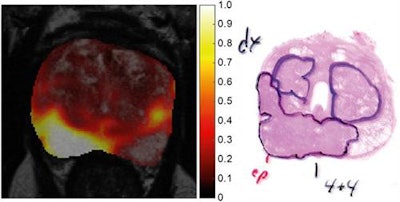

Images show a central slice (left) through tumor probability map of a 64-year-old patient, fused with T2-weighted MR image for anatomic reference. Region with highest tumor probability values (right) correspond to peripheral-zone tumor with Gleason score of 4 + 4, as verified by histopathology. Images courtesy of Journal of Nuclear Medicine."We found that when we combined the information from multiparametric MRI and fluciclovine-PET, we were better able to distinguish tumors from other tissue than using only multiparametric MRI or only fluciclovine-PET," said lead author Mattijs Elschot, a researcher at the Norwegian University of Science and Technology in Trondheim. "We believe these results are a good example of the versatility and complementarity of prostate PET/MRI."